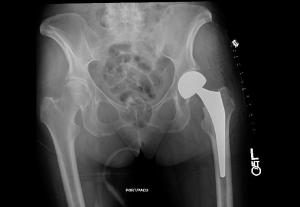

El problema principal de las fracturas intracapsulares es que se interrumpe la circulación de la cabeza femoral, vamos que se decapita cuanto más desplazada está. Es un problema biológico. Si está muy poco desplazada y el paciente es joven intentamos sintetizarla (recomponerla) cuanto antes, pues cuanto más tiempo pase más probabilidades hay de que la circulación sufra daño. Para ello podemos usar unos tornillos de osteosíntesis. A veces no es suficiente y pasados unos meses la cabeza del fémur al quedarse sin circulación se necrosa (una especie de infarto), en ese caso optamos por una prótesis de cadera. En pacientes ancianos, que son la mayoría, optamos casi directamente por una prótesis de cadera, pues ya de por sí el estado de la cabeza no es muy bueno y no nos arriesgamos a que la cabeza infarte, además la prótesis nos permite andar a los pocos días. Si alguien se pregunta por qué no optamos directamente en jóvenes por la prótesis creo que la respuesta cae de cajón, conservas tu propia “cabeza femoral” sin necesidad de pensar que en cierto tiempo puede ser necesario recambiar la prótesis. No me voy a extender en el tipo de prótesis que usamos, quizá para otro post. Ahora lo más importante es saber que en las fracturas “de cuello femoral” se suelen usar prótesis y en algunos casos seleccionados tornillos para conservar la cabeza del fémur.

[caption id="attachment_399" align="alignnone" width="300"]Protesis cadera (hemiartroplastia) Protesis cadera (hemiartroplastia)